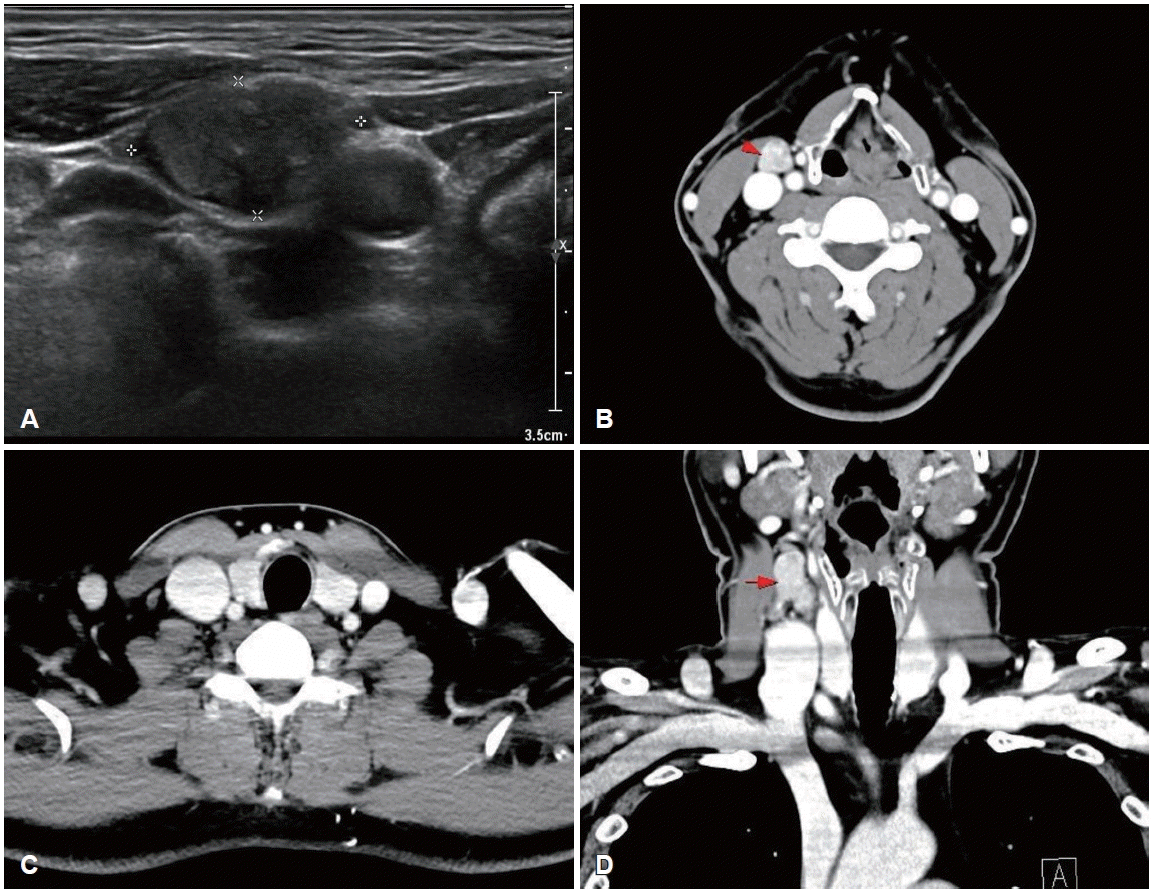

Preoperative ultrasonography and CT findings. A: An oval-shaped, well-defined, heterogeneously hypoechoic mass measuring 2.04×1.11 cm with low vascularity and loss of the hilum is present at right cervical level III. B-D: Axial (B and C) and coronal (D) contrastenhanced CT images show an approximately 14×15×21 mm, well-marginated, heterogeneously enhancing solid mass-like lesion at right level III (red arrows) and no definite space-occupying lesion in either thyroid lobe.

A 50-year-old male was referred to our outpatient clinic after incidentally detected cervical masses during an ultrasound-guided procedure for neck pain at a local clinic 3 weeks ago. Local ultrasonography revealed heterogeneous masses of varying sizes in the right neck. He was asymptomatic, had no underlying disease, and no palpable mass was detected on physical examination. On the day of presentation, repeat ultrasonography demonstrated a 2.04×1.11 cm oval-shaped, well-defined, heterogeneously hypoechoic mass with low vascularity and loss of the fatty hilum at right level III (Fig. 1). The sonographic appearance did not specifically suggest metastatic PTC; rather, a neurogenic tumor was favored because of the mass morphology and perivascular location. No suspicious lesions were identified in the thyroid parenchyma or salivary glands. Because pathologic confirmation was required to guide management, fine-needle aspiration of the mass was performed simultaneously and revealed metastatic PTC; nuclear enlargement, multiple nuclear pseudoinclusions, and grooves were noted with positive immunohistochemical staining for thyroid transcription factor-1 (Fig. 2).

The biopsy report was explained to the patient and after counseling, the patient elected surgery to remove a presumed occult thyroid primary and any additional nodal disease. Contrast-enhanced neck CT was subsequently obtained to evaluate the thyroid gland and additional cervical metastases before surgery and no other imagaing study was performed. No definite lesion was identified in both thyroid lobe, and only a single enlarged right level III lymph nodes were observed (Fig. 1). Total thyroidectomy with right selective neck dissection (levels II-IV) and central compartment node dissection was performed in accordance with 2015 American Thyroid Association (ATA) guidelines to remove hidden malignancy in thyroid gland, to enable postoperative serum thyroglobulin (Tg) monitoring for recurrence detection and to allow radioactive iodine (RAI) ablation if needed [3]. A firm 3.0×2.0 cm mass was noted at right level III, and a firm 0.5 cm nodule at the superior thyroid isthmus was suspicious for micro-PTC. Both recurrent laryngeal nerves were identified and preserved. Pathologic examination showed no abnormality in either thyroid lobe, and the palpable isthmic nodule represented nodular hyperplasia (Fig. 3). Total 11 lymph nodes of 28 were found metastatic PTC and single node with extranodal extension (ENE) at right level II was identified with 18 mm of largest dimension; metastatic involvement included 5 level VI nodes of 9 without ENE, 5 right level II nodes of 7 with ENE, and 1 right level III node of 8 without ENE; no level IV nodes were involved (0/4). Postoperatively, both the resected lymph nodes and the isthmic nodular hyperplasia were tested for BRAF mutation, and all results were negative.